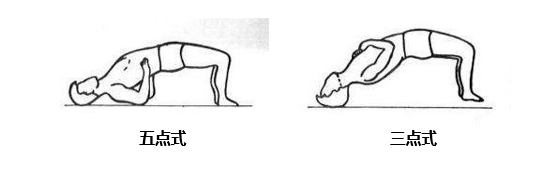

⑤ 功能鍛煉

緩解期即開始腰背肌功能鍛煉,加強腰背肌保護功能。

五點式鍛煉:把頭部、雙肘及雙足跟作為支撐點,使勁向上挺腰抬臀。

三點式鍛煉:腰背肌功能加強后可改用頭部及足跟三點作為支撐的“三點式”鍛煉方法。

當然,以上鍛煉需循序漸進,逐漸增加,避免疲勞。如果經保守治療6-12周出現(xiàn)癥狀無明顯好轉,癥狀急性或進行性加重,應考慮行手術治療,以防延誤手術時機。

2、功能鍛煉

患者在臥床休息期間為了防止神經根粘連,加強腰椎的穩(wěn)定性,可在床上做直腿抬高練習、“五點支撐”、 “三點支撐”等鍛煉方式進行功能鍛煉。